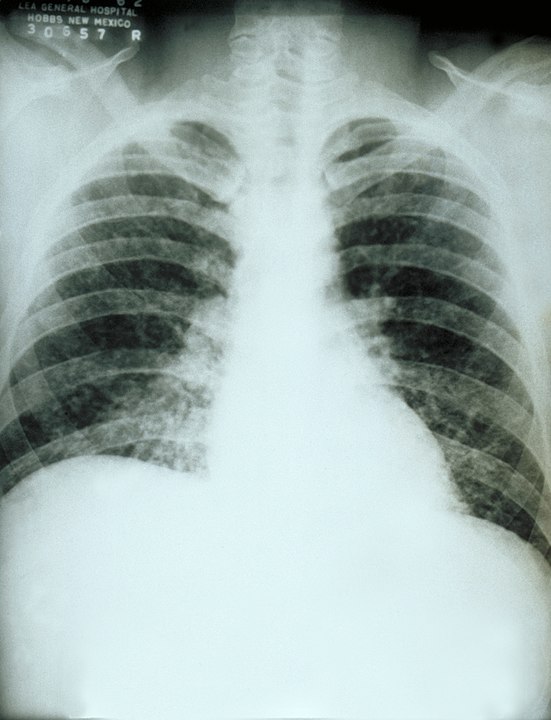

X-rays showed nodules in her lungs and tests showed low blood counts. Her condition baffled local doctors, who initially thought her lung infection could be some form of pneumonia.